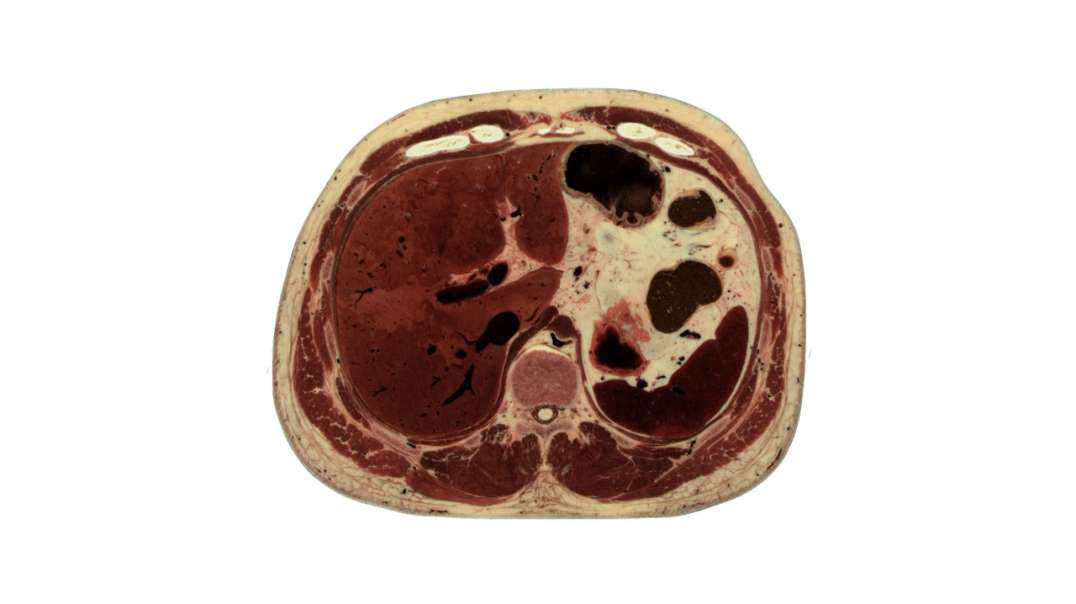

4th lumbar vertebra level

4th lumbar vertebra level kenhub